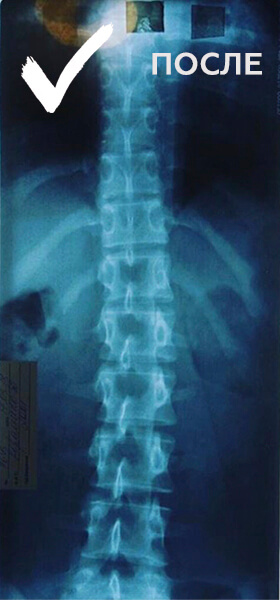

5 МЕСЯЦЕВ ЗАНЯТИЙ В DORSUM

ДЕВОЧКА, 16 ЛЕТ